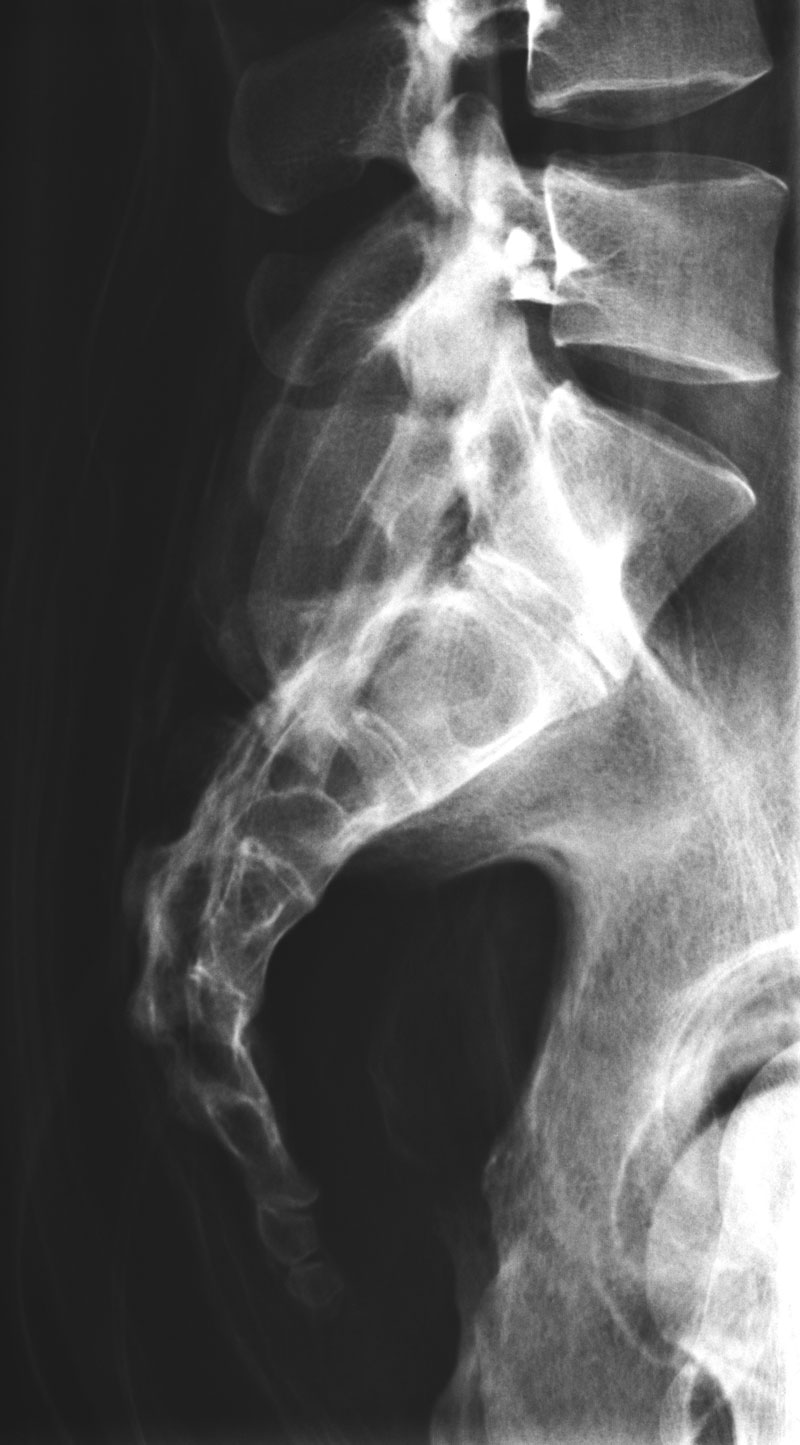

Dieses weltweit einmalige Phantom bietet erstklassige Übungsmöglichkeiten für die Lagerungs- und Einstelltechnik in der Projektions-Radiographie und gehört eigentlich zur Grundausstattung jeder Röntgen-Ausbildungsstätte.

Das Phantom enthält ein natürliches menschliches Skelett, dadurch können mit dem Phantom echte Röntgenaufnahmen wie beim Patienten gemacht werden.

Durch die Verwendung des echten Skeletts können Leitstrukturen im Knochen erkannt werden, was bei Kunststoffskeletten nicht möglich wäre. Bei der Montage des Phantoms wird besonderer Wert auf die Darstellung der Gelenkspalte gelegt.

Die Gelenke sind beweglich montiert und ermöglichen die Lagerung in den normalen Röntgenpositionen.

Die Arme können nach oben bewegt werden, so dass das Modell auch für alle knöchernen Untersuchungen im CT verwendet werden kann. Bei jedem Phantom handelt es sich um ein handgefertigtes Unikat, welches sich in Größe und Ausführung unterscheiden kann.

Je nach Modell können pathologische Befunde vorhanden sein, die äußere Erscheinung kann sich je nach Größe des Modells unterscheiden. Die neue Ausführung dieses Modells wurde in Zusammenarbeit mit einer namhaften deutschen Schule für Med. Techn. Radiologieassistenten komplett überarbeitet und erfüllt alle Anforderungen für die Ausbildung.

Der Verkauf dieses Phantoms erfolgt nur gegen Nachweis der medizinischen Verwendung. Natürliche Größe.

7200

GANZKÖRPER RÖNTGENPHANTOM

24.957,98 € (29700,00 €)